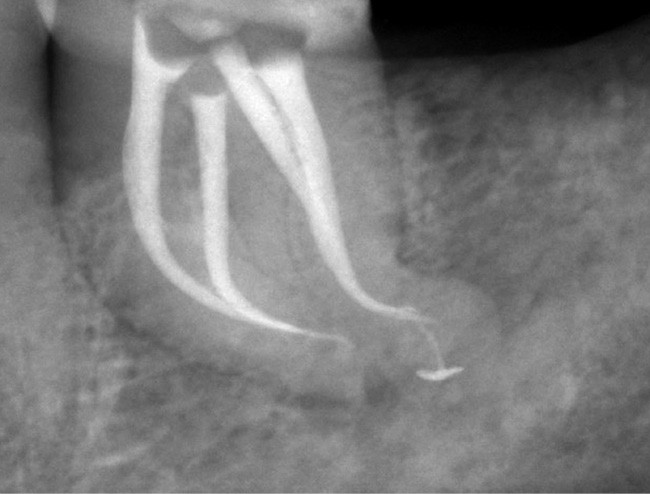

Le nettoyage des isthmes intercanalaires reste un réel problème, et semble responsable de nombreux échecs [43]. Par ailleurs, il est nécessaire d’utiliser des instruments qui évitent de propulser les débris, tant apicalement que latéralement, en obturant les entrées isthmiques avec des débris compactés.

L’utilisation d’instruments en nickel titane, tels que le XP Shaper (FKG), le Vortex blue (Dentsply) ou le Profile (Dentsply), optimise la remontée des débris et s’inscrit dans cette nouvelle philosophie. En conséquence, la combinaison XP Shaper, XP Finisher et l’irrigation avec l’Er:YAG semblent optimiser nos traitements [44,45].

Le passage du laser est répété plusieurs fois, en début, au milieu et en fin de préparation. Un protocole peut alors être proposé : 40 mJ ; 20 Hz (fig. 7). L’utilisation de biocéramiques Bioroot (Septodont) ou Total Fill R (FKG) permet de sceller le système ainsi nettoyé, en assurant une action biologique de longue durée [46] (fig. 8a à c).